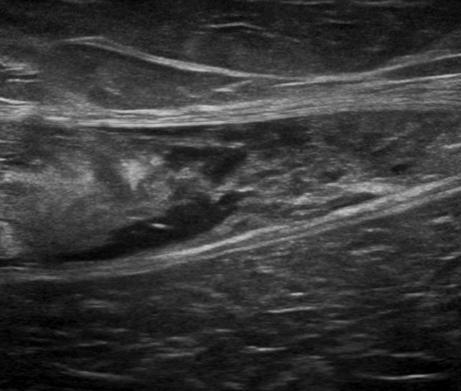

Chấn thương thành bụng

» Thông tin: Nam giới – 50 tuổi.

» Lâm sàng: Chấn thương thành bụng.

# Đụng dập, tụ máu cơ thành bụng.